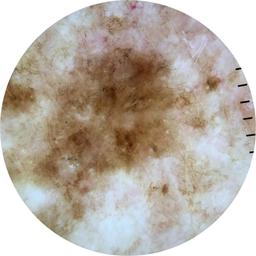

{

"age_approx": 70,

"anatom_site_general": "posterior torso",

"concomitant_biopsy": true,

"diagnosis_1": "Malignant",

"diagnosis_2": "Malignant melanocytic proliferations (Melanoma)",

"diagnosis_3": "Melanoma, NOS",

"diagnosis_confirm_type": "histopathology",

"fitzpatrick_skin_type": "II",

"image_type": "dermoscopic",

"lesion_id": "IL_0852638",

"melanocytic": true,

"patient_id": "IP_8502723",

"sex": "male"

}